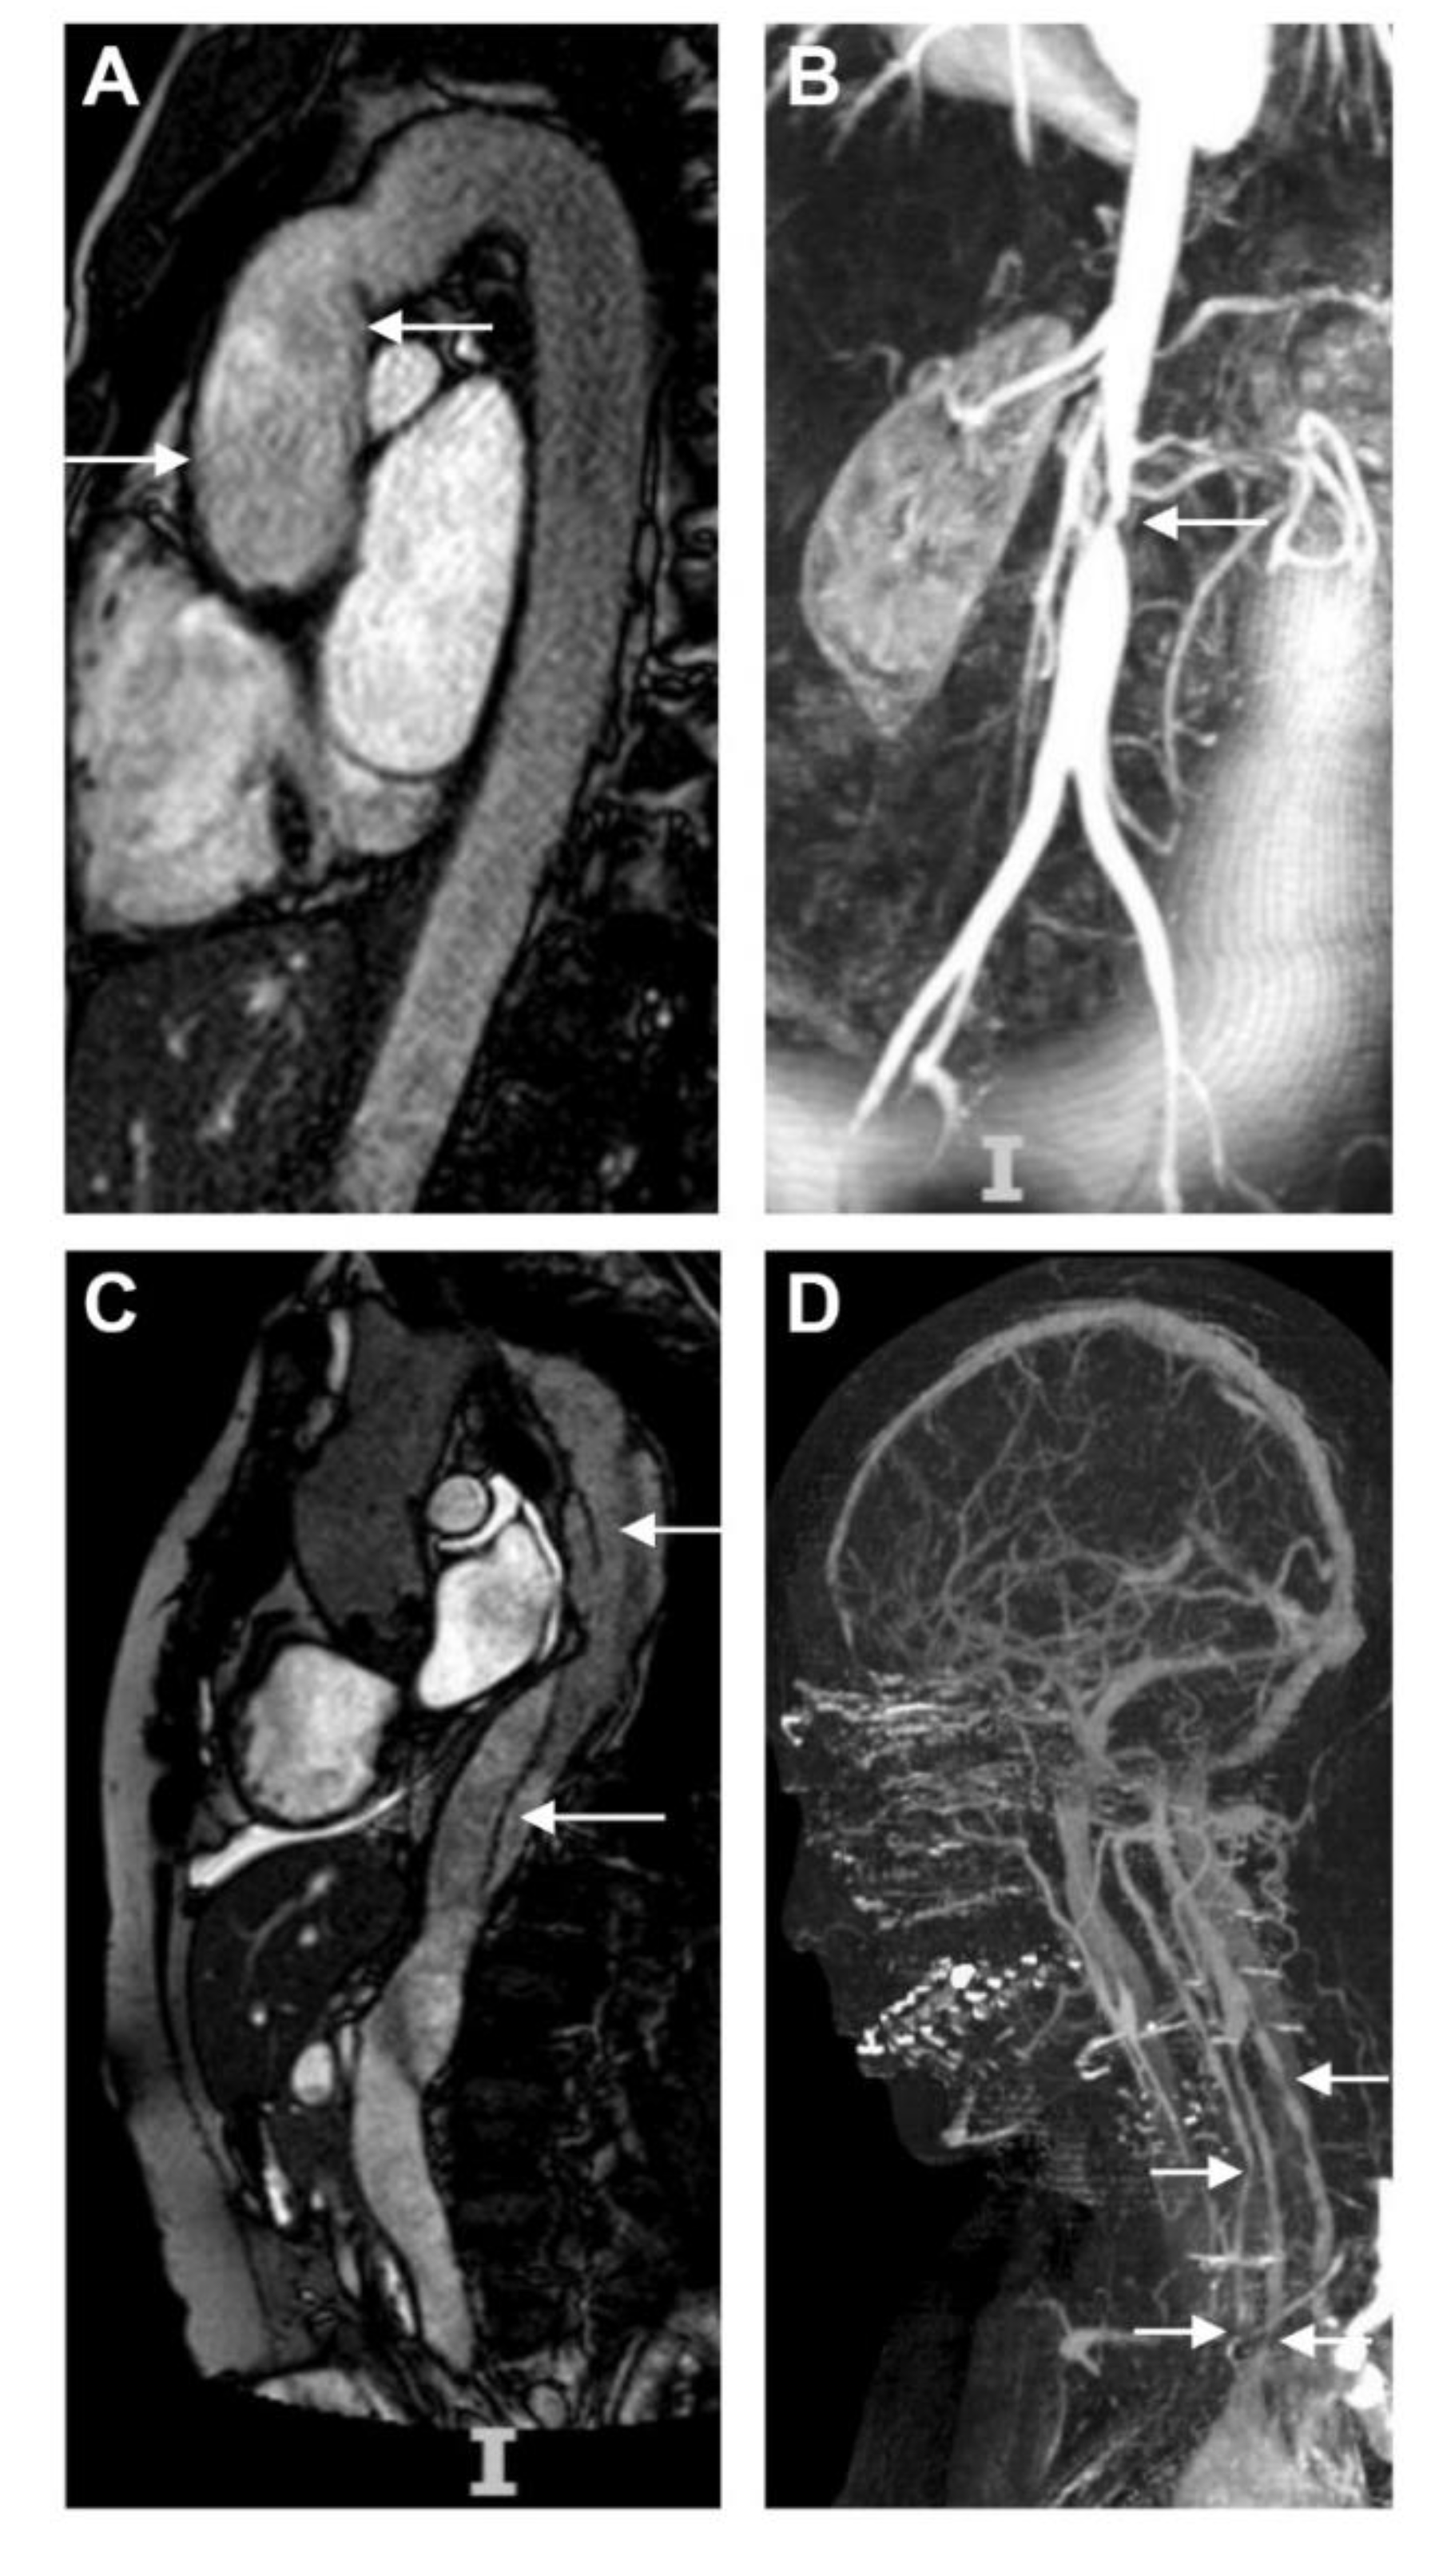

6. Pre-Operative Assessment of Disease Activity

8.1. Supra-Aortic Disease and Cerebral Ischemia

8.4. Coronary Arteries

8.5. Visceral Arteries